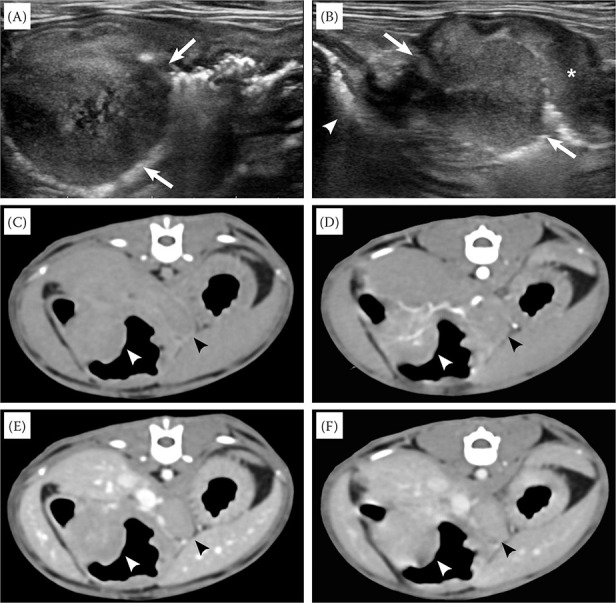

A 6-month-old Ragdoll and 9-year-old Russian Blue cat presented with vomiting. Ultrasonography and computed tomography showed a pyloric antrum mass with wall layering loss and regional lymphadenopathy in the Ragdoll kitten. The Russian Blue cat only presented with muscularis layer thickening throughout the jejunum; however, despite medications, it later progressed to a mass with wall layering loss on the serial ultrasound. Both cats underwent surgery, and feline gastrointestinal eosinophilic sclerosing fibroplasia (FGESF) was histologically confirmed. FGESF should be considered for gastrointestinal masses demonstrating wall layering loss and lymphadenopathy, even in kittens, and intestinal muscularis layer thickening that is refractory to medications.